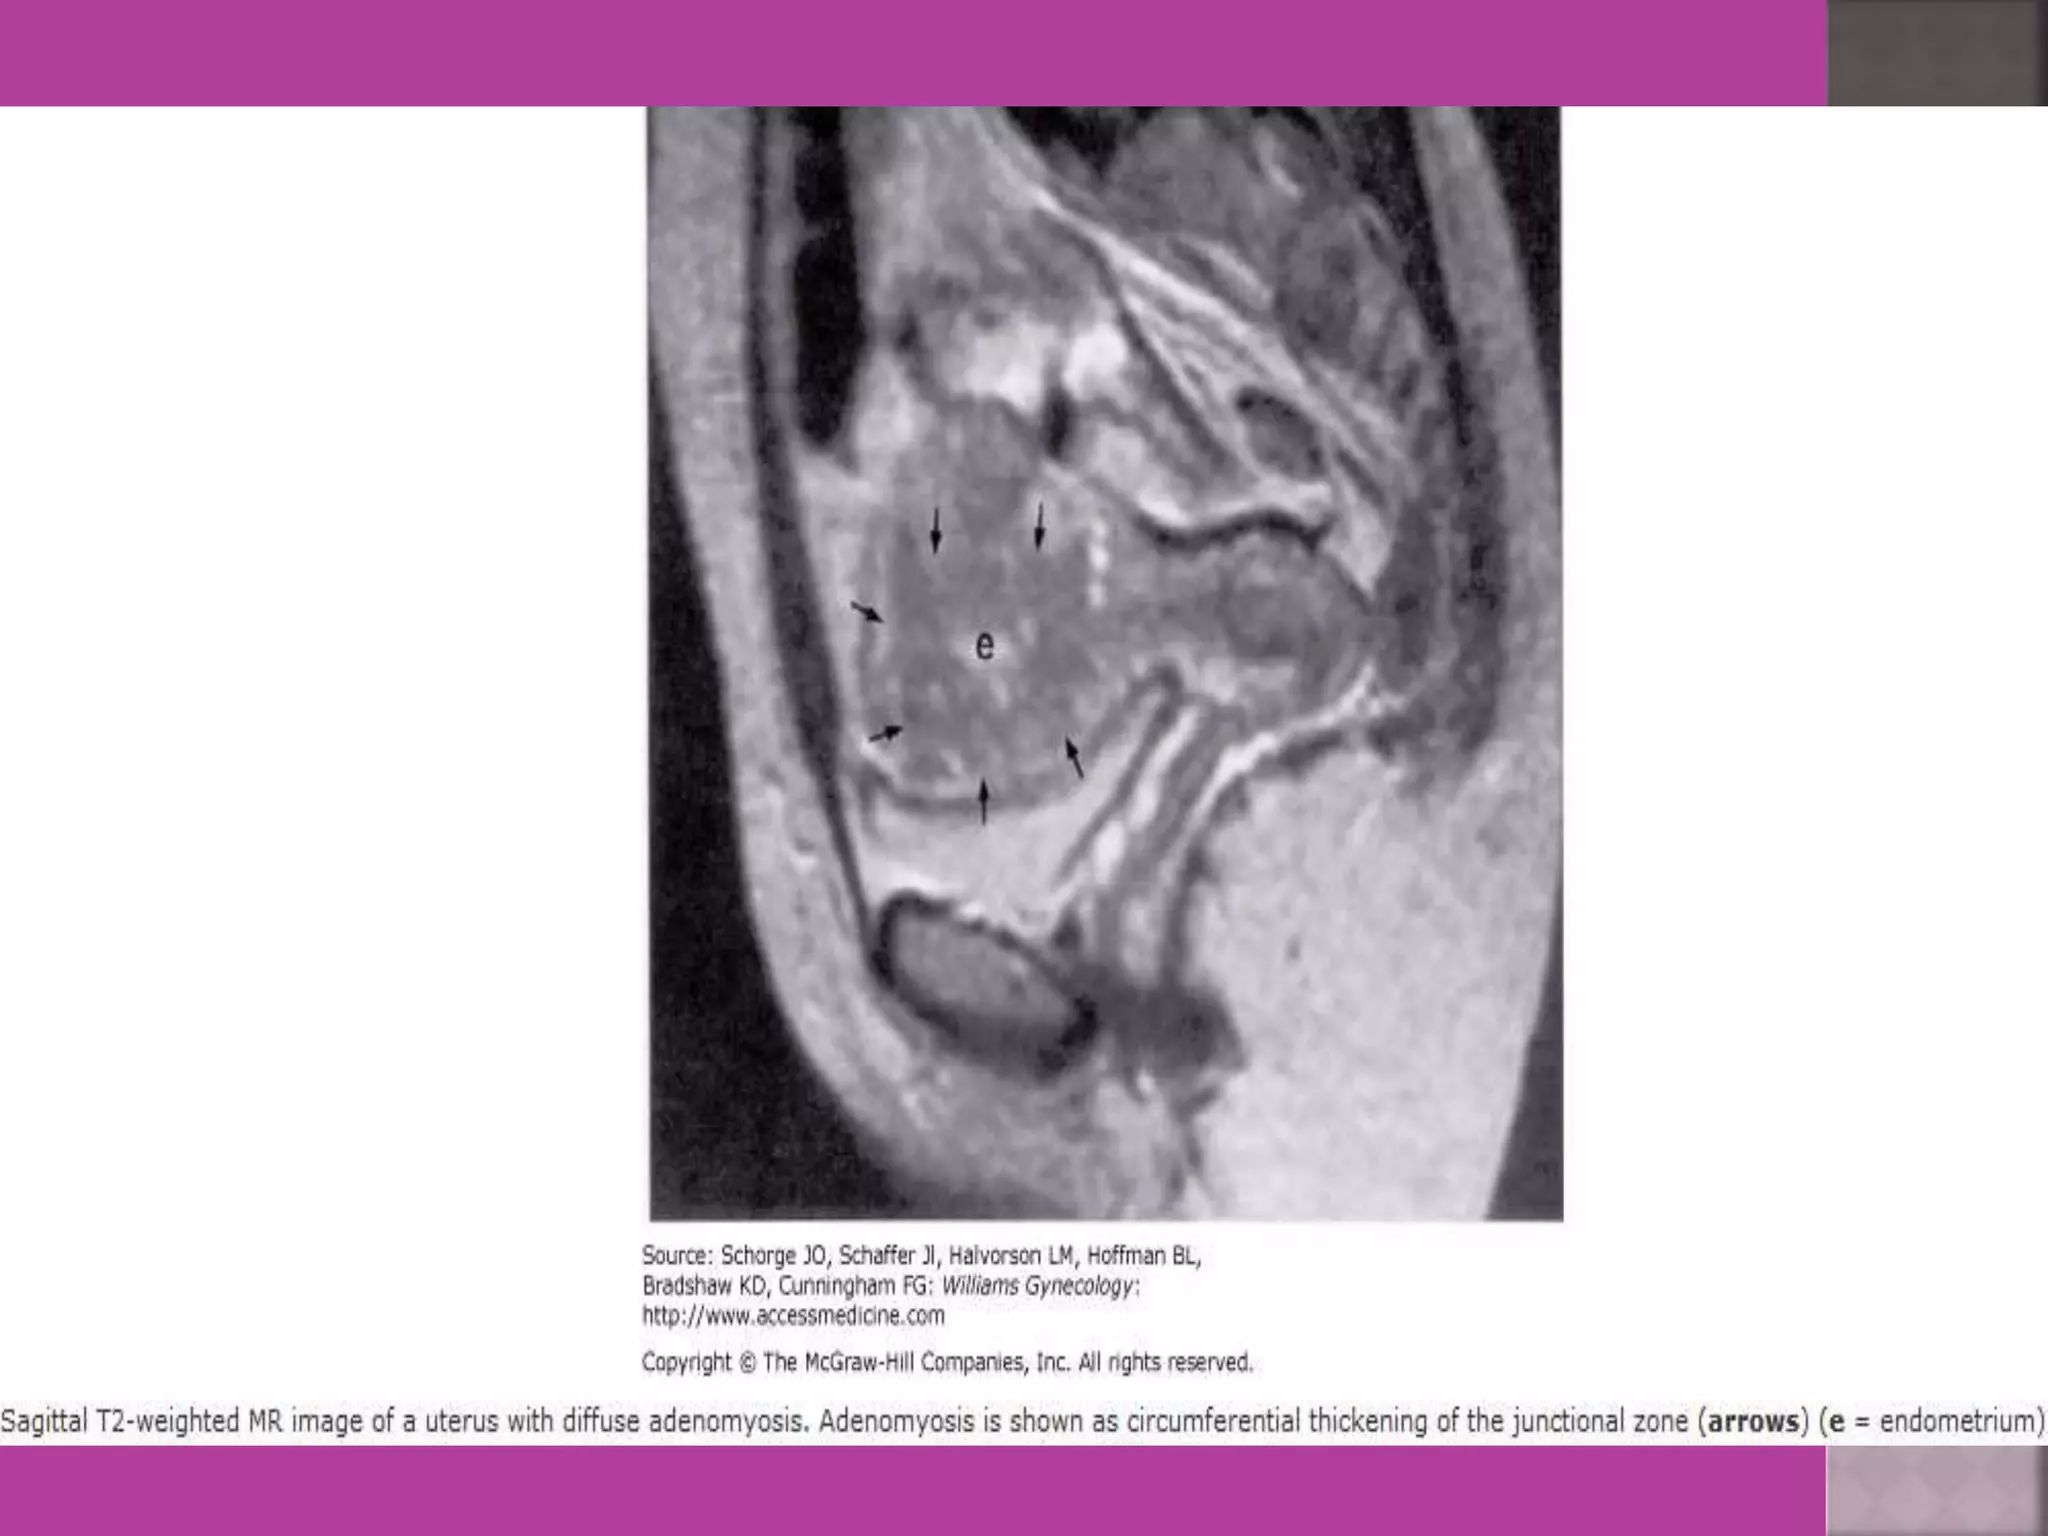

 MRI is most sensitive for diagnosis of Adenomyosis.

 MRI ismost sensitive for diagnosis of Adenomyosis.  MRI Is more accurate and informative in diagnosis of congenital malformation of genito-urinary tract.  Retroparitoneal lymph node > 1cm can be identified so also such small deposits on bowel / bladder liver can be identified in cases of cancers.  It is more sensitive and accurate tool to assess infiltration of myometrial/ cervical wall, adjoining organs and parametrium --thus helps in pre operative staging of genital carcinomas.  As it is safe in pregnancy –it is useful in diagnosis of obstetrical conditions as well s differentiation of tumors (benign / malignant ) complicating pregnancy.